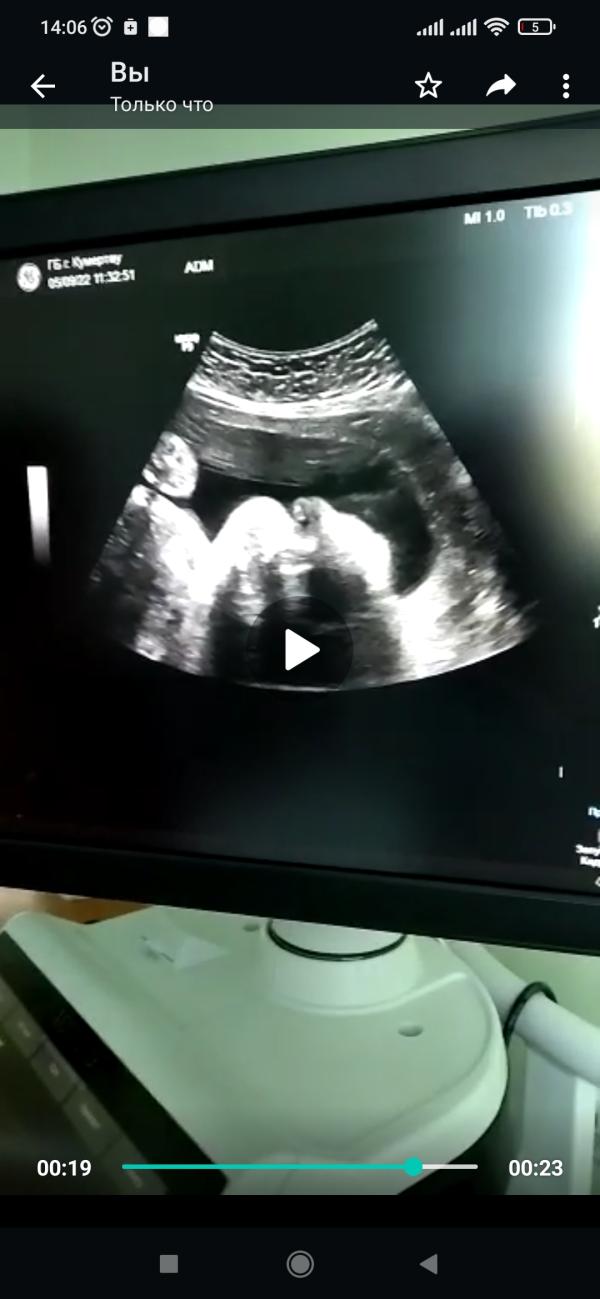

На память 😍

31н. 1830г